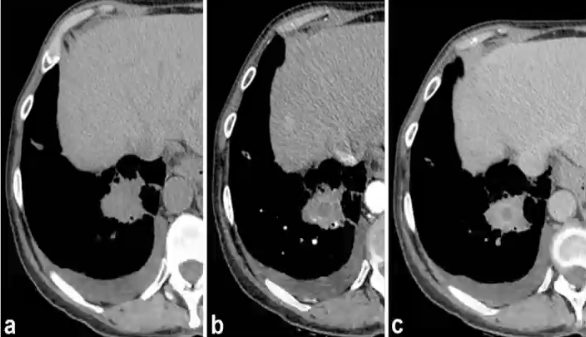

低密度征(hypodense sign,HyS)

❖ 定义:实变或结节中心低密度影-中心坏死

❖ 病理基础:血管阻塞致肺梗死和隔离

❖ 平扫检出低,增强检出高

❖ 在高度怀疑真菌感染的粒缺患者中,HyS特异性高,但敏感性较差

❖ HyS有助于鉴别细菌真菌感染,早期启动抗真菌治疗